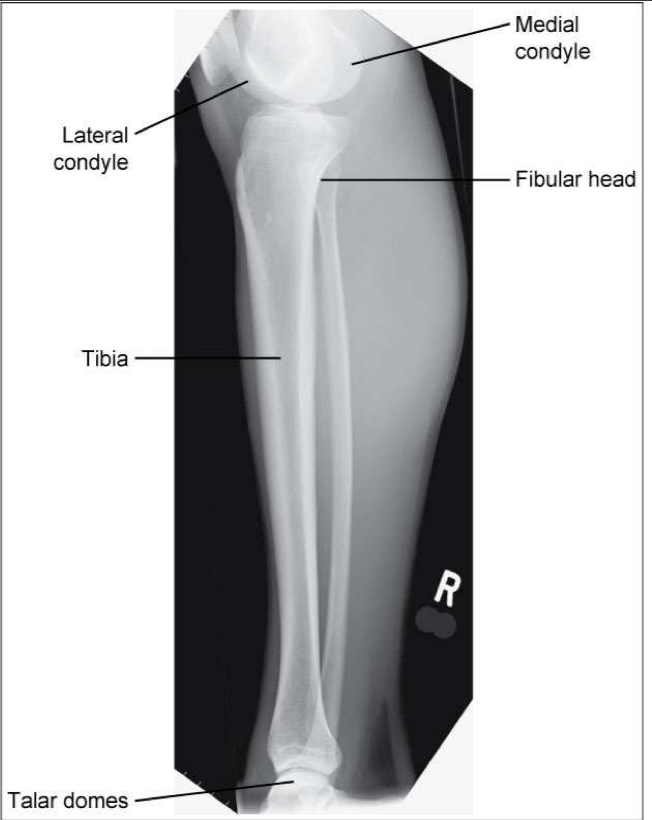

AP Tibia & Fibula

Patient Position

• Lying on x-ray table

• Affected leg extended

Part Position

• Entire affected limb is in a true AP

• Affected foot is dorsiflexed 90o

CR

• perpendicular to the IR; centered to midshaft region of tib/fib

Collimation

• Knee to ankle must be included

Usually requires the IR to be placed diagonally

May also require increase SID

Evaluation Criteria for AP Tib/Fib

• Entire tibia and fibula demonstrated

• Knee and ankle joints demonstrated

• Partial superimposition of fibula and tibia at proximal and distal ends

Due to divergence of the beam, neither knee nor ankle joint is fully open

• Optimal exposure factors